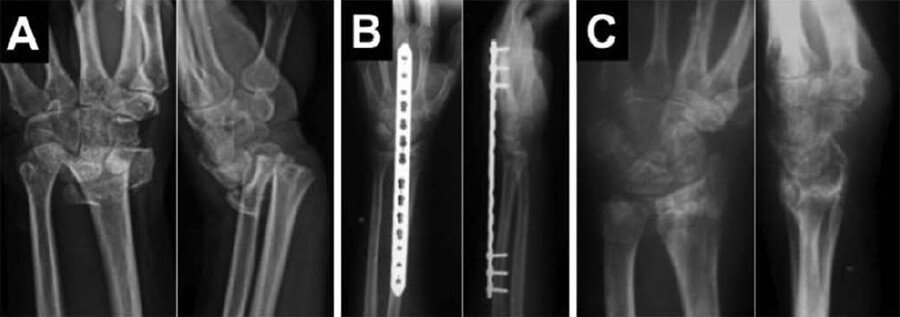

Ahora bien, 5 (55,55%) pacientes pudieron reintegrarse nuevamente a sus actividades laborales, mientras que los otros 4 (44,44%) se ocupaban de los oficios del hogar, y lo siguieron haciendo sin problemas. Ningún paciente presentó signos sugestivos de infección, no hubo casos de osteomielitis o ruptura del algún tendón extensor. No se reportaron complicaciones relacionadas con la implantación ni el retiro del implante. Específicamente, no hubo ninguna lesión tendinosa, refractura, pérdida de la reducción o pérdida de longitud radial. Ningún paciente presentó rigidez digital. En las Figuras N° 4 y N° 5 presentamos uno de los casos de esta serie.

Figura N° 4.

Paciente 3: Femenino de 58 años. Radiografía posteroanterior y lateral de la muñeca a su ingreso (A), en el post operatorio inmediato (B) y a los 7 meses del post opateratorio (C).